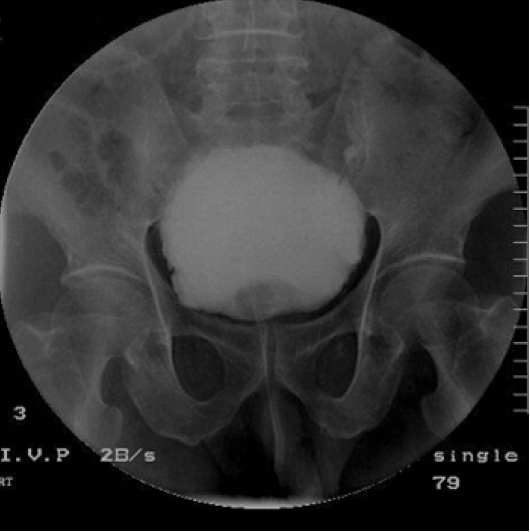

치료 및 경과: 수술 전 처치로 8시간 동안 금식을 하였으며 수술 직전 배뇨를 하였다. 수술은 국소 마취로 개복 없이 Tenckhoff 트로카를 사용하여 정중 절개법으로 시행하였다. 수술 후 환자가 자가 배뇨를 하지 못하여 도뇨관을 삽입하였다. 복강 내 세척을 위해 투석액 주입 및 배액을 반복하던 중 배액량이 적고, 도뇨관으로 투석액이 배액되는 것이 관찰되어 수술 중 방광 천자가 의심되었다. 방광 조영술을 병행한 컴퓨터 단층 촬영술(retrograde CT cystography)에서는 복막 투석 도관의 일부가 방광 내에 위치하고, 도뇨관을 통해 주입한 조영제가 복강 내로 유출되는 것을 확인하였다(Fig. 1). 이후 30분 뒤 재수술을 시행하여 방광 내로 삽입된 복막 도관을 제거하고, 도뇨관의 유지와 예방적 항생제 사용 등의 보존적 치료를 하였다. 소변량은 매일 1.5-2 L 정도로 유지되었고 발열이나 복통 등의 증상은 없었다. 일주일 후 신대치 요법을 위해 속목정맥 도관을 이용하여 혈액 투석을 시행하였다. 도뇨관 유치 후 14일째 역행성 방광 조영술을 실시하여(Fig. 2) 조영제의 유출이 없음과 방광 내벽의 무결성이 확인되어 도뇨관을 제거하였다. 이후 동정맥루 수술 후 퇴원하여 현재 주 3회 혈액 투석 시행 중이다.